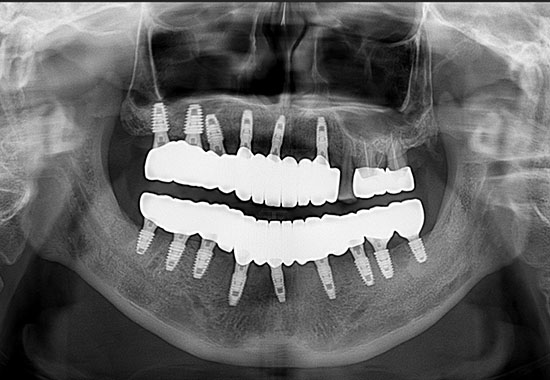

BEFORE

AFTER

- 식립 개수 : 15개 (상악 9개 하악 6개)

- 수술 내용 : 교합 거상, 크라운, 임플란트